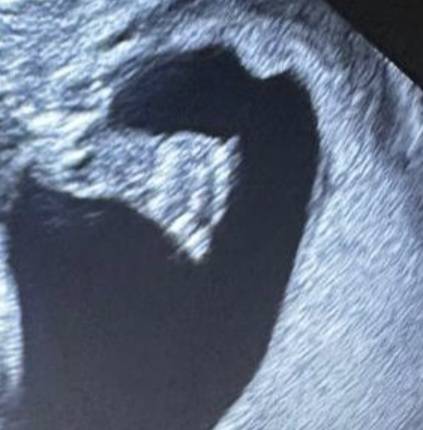

На УЗИ врач сказал, что скорее всего мальчик и девочка 🐰🦊

И это уже второй врач,который так сказал😍

Самое главное, что малыши здоровы🙏

На фоточке ступня👀и даже уже видно пальчики😍